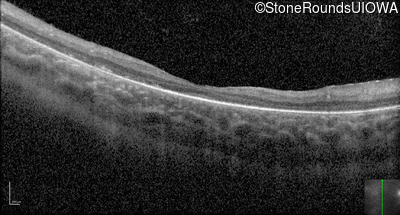

Optical Coherence Tomography - Right - 10/600 sc

Exemplar / OCT Stack

Optical Coherence Tomography - Left - 10/600 sc